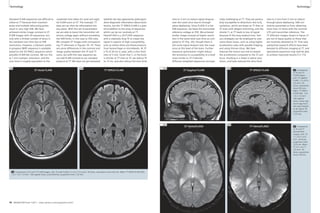

Healthy Osteoarthritis

Anatomical image T2 (ms) Anatomical image T2 (ms)

4A

4B

0 35 0 35

ADC (10-3mm2/s) FA ADC (10-3mm2/s) FA

4C 4D

4E 4F

4G 4H

0 2.5 0 1 0 2.5 0 1